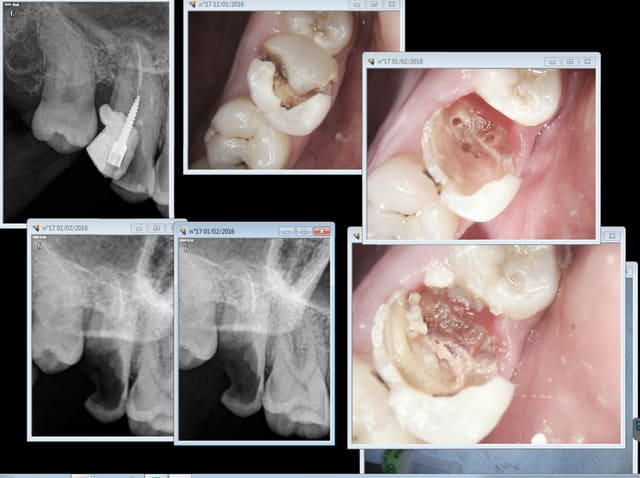

j'ai pu travailler sur un implant en place de 17 sans faire dans mon froc

Pour moi, le principal inconvénient est l'encombrement. En endo, c'est infiniment plus rapide que de faire une reconstitution pré endo, et pour les fluides, il faut compléter par une aspiration à proximité de la dent au moment de l'irrigation

on enlève pas l'isolite, le capteur est coincé par la languette qui récline le plancher de la bouche et la langue. De plus le patient détendu ne tend pas le mylo hyoïdien au moment de l'insertion du capteur

C'est vrai. Le cas suivant était déjà limite mais en plus j'ai pété un sx dans le MV1 et ca s'est terminé en extrac. C'est con les 3 autres je les avais bien. -)

mais ou est la recontitution préendo chicot ?